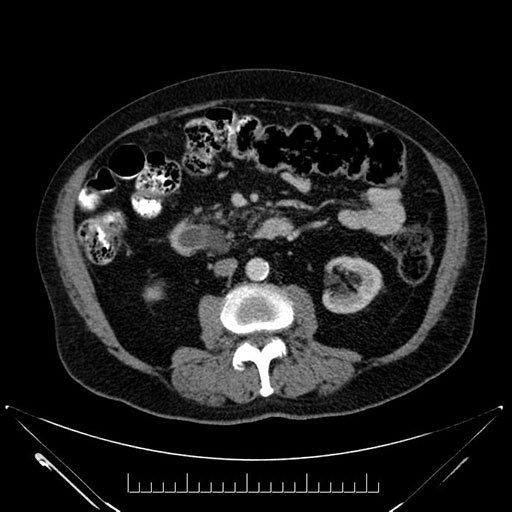

Whipple (pancreaticoduodenectomy) [case 7]

Imaging Analysis

Look through the patient's CT scan to identify any areas of concern for the necessary procedure.

Based on your CT findings, which issue(s) would give reason for "planned slowing down moment(s)" in this case?

Considering a standard Whipple procedure, what step(s) of the operation would you do differently in this case?